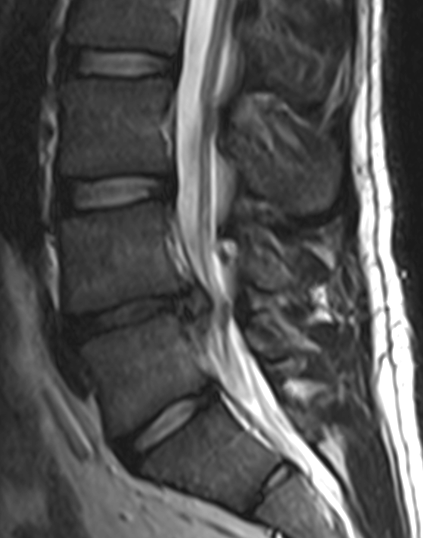

Diagnostic tests: Generally, we start with plain x-ray films, which allow us to rule out other problems such as pelvic instability or joint compression. If there is a need for further studies, CT scans and MRIs are often used to give us three-dimensional views of the lumbar spine and can help detect herniated discs.